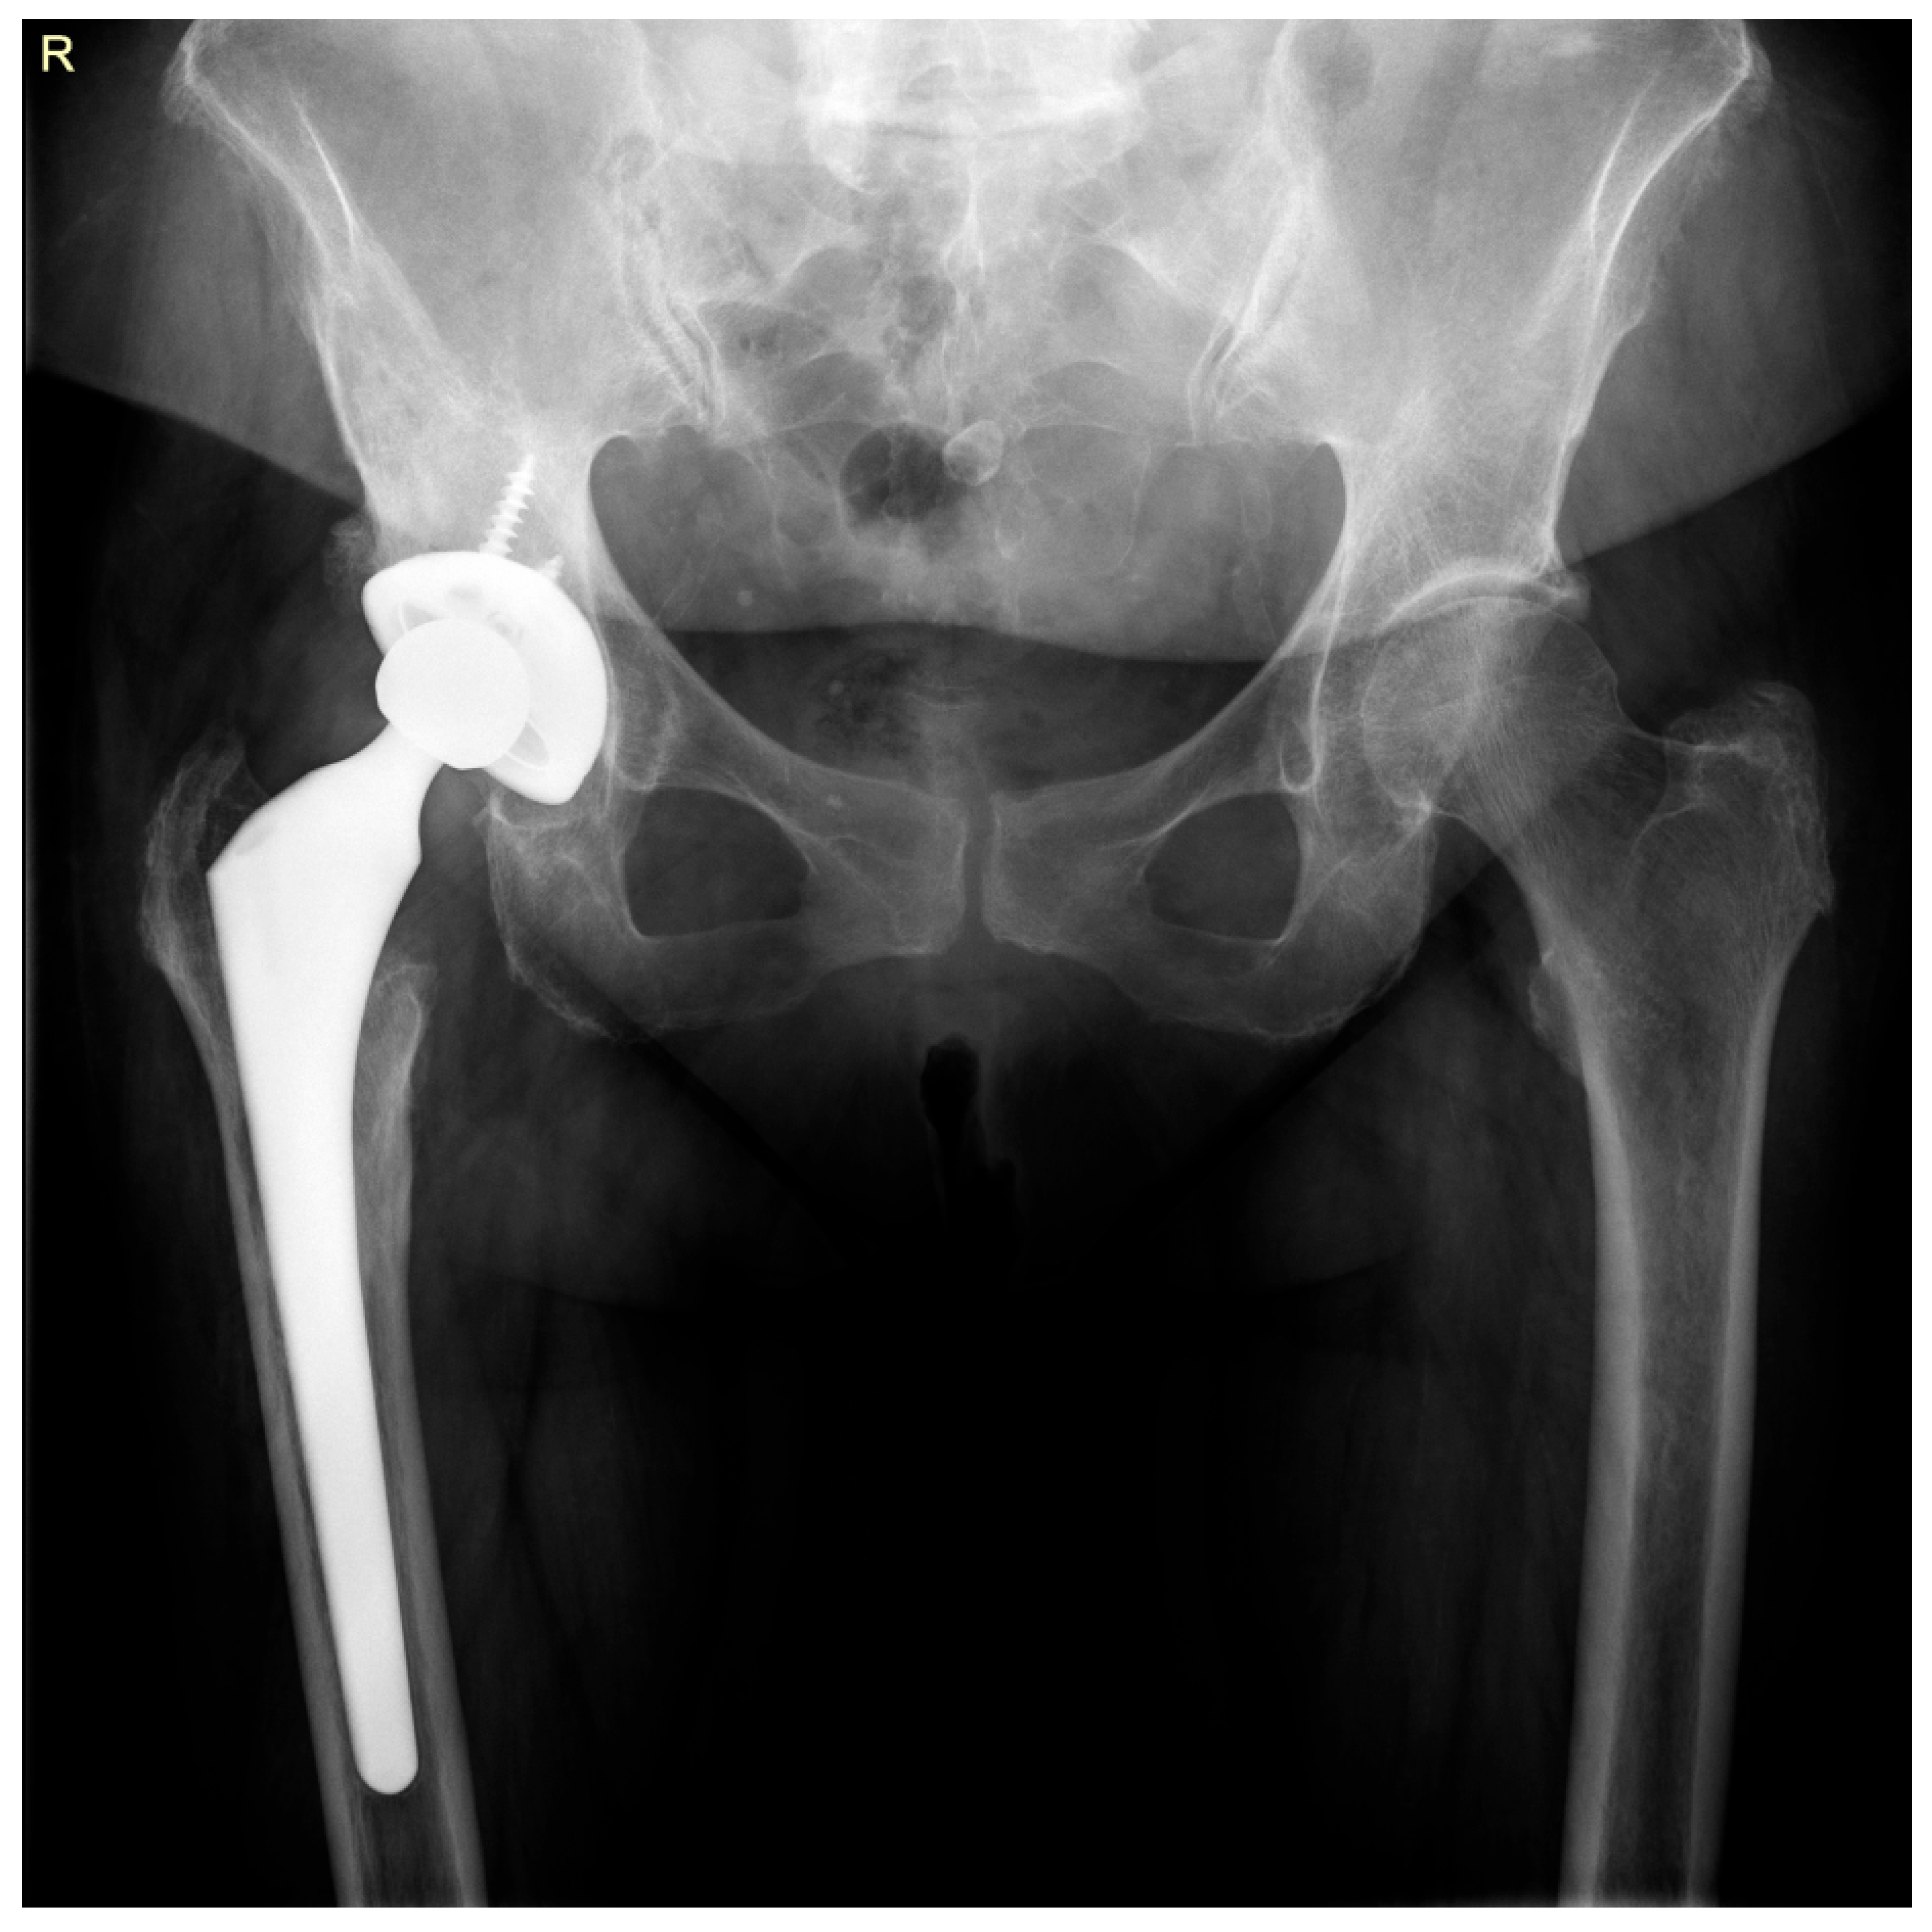

2. Case Report